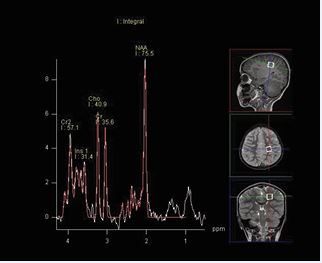

MRI technique: The protocol consisted of axial T1, axial FLAIR, axial DWI, axial SWI, coronal T2, and sagittal T1 sequences. Proton MR spectroscopy was performed in all patients by using a single voxel point-resolved spectroscopy (PRESS) sequence with a repetition time (TR) of 1500 ms and two echo times (TE) of 144 milliseconds (ms) and 35 ms, voxel size of 15 mm were used. As illustrated in Figure A and B, two locations were assessed with both the long and short TE MRS. One in the frontoparietal deep white matter and the other in the basal ganglia. The metabolites assessed include NAA, choline, creatine, myo-inositol, and lipids/lactate. All MRI examinations were reviewed by an experienced pediatric neuroradiologist.Data were coded and recorded in an Excel spreadsheet program. Statistical Package for the Social Sciences (SPSS) software, Version 27.0.0.0 (IBM Corp., Armonk, NY) was used for data analysis. A descriptive analysis of the experience of the participating groups was provided.

Figure A: Single-voxel PRESS acquisition in the frontoparietal deep white matter.